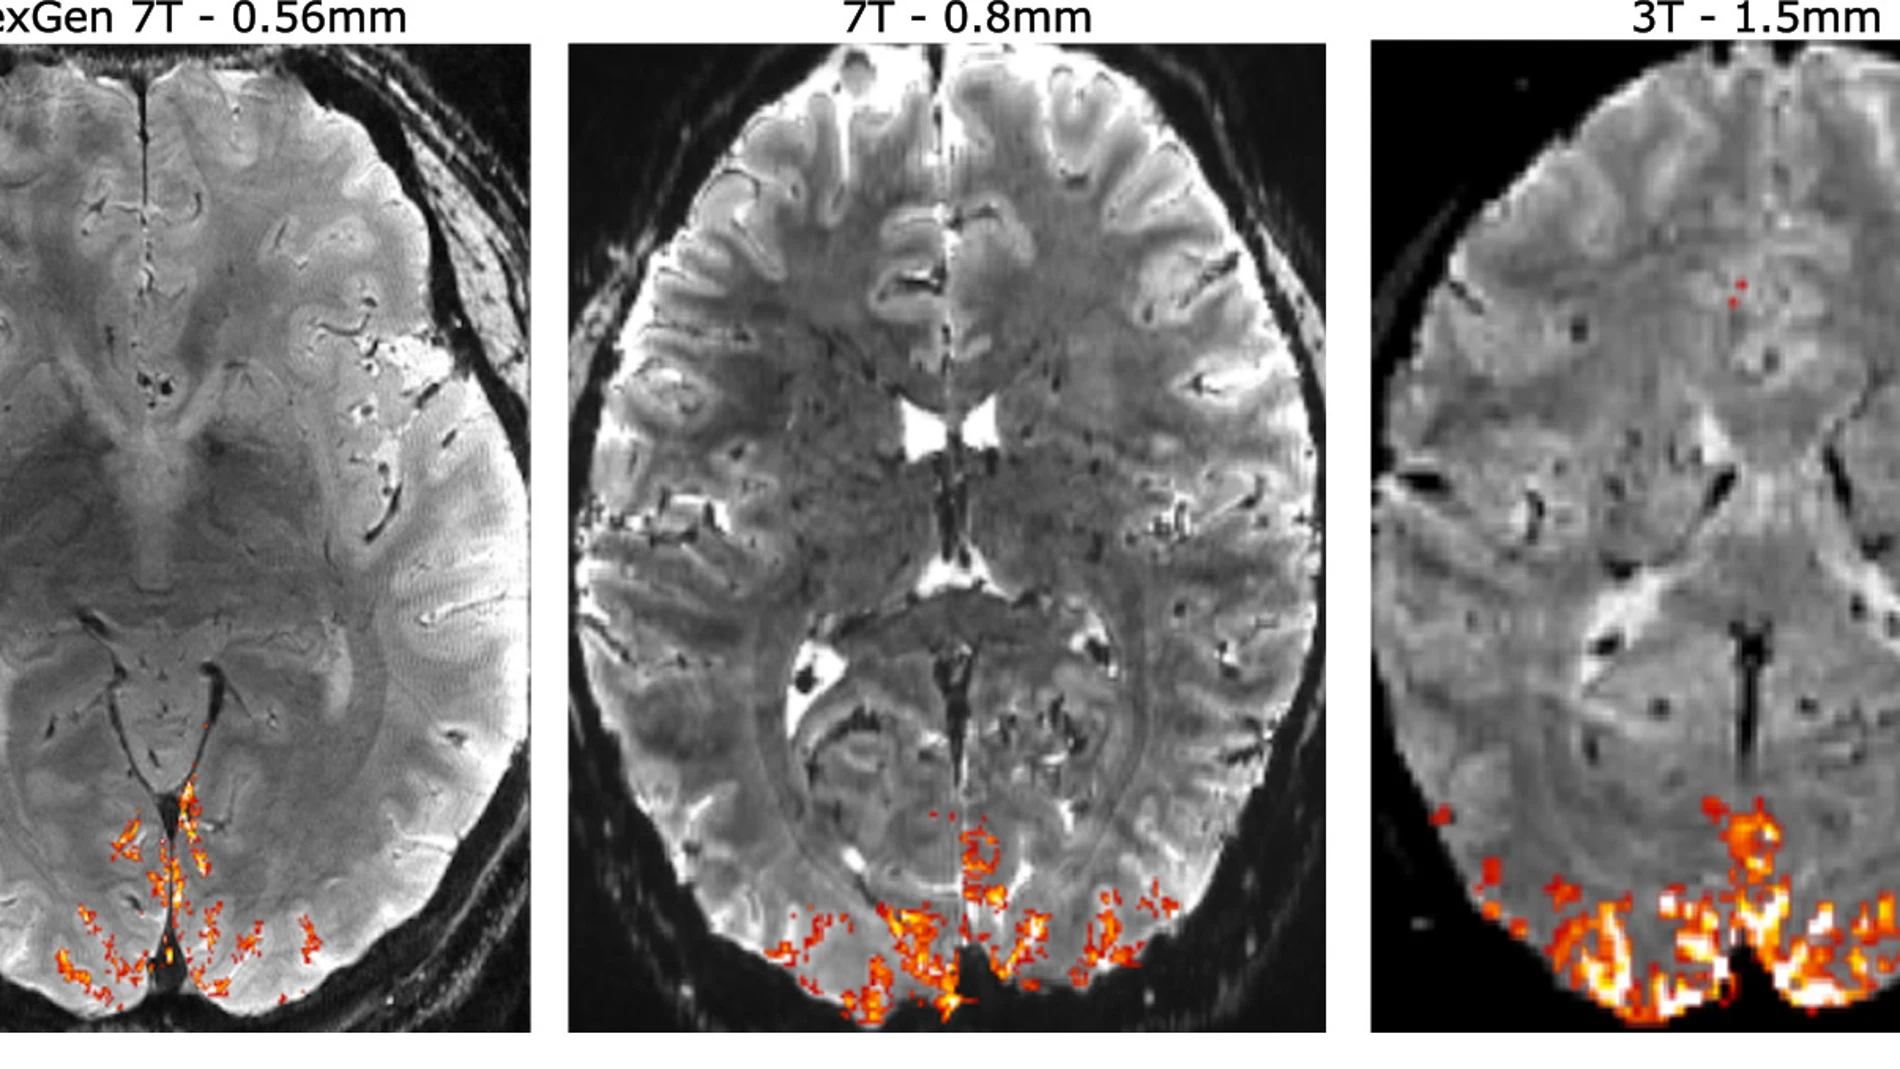

Los psicópatas exhiben una activación muy baja en la amígdala que está directamente relacionada con el miedo, al tiempo que presentan una menor producción de serotonina, una circunstancia que influye en el carácter desinhibido de su conducta.

Su falta de ansiedad y evasión de situaciones amenazantes se atribuye a la inexistente activación de la amígdala y al débil impacto emocional que no se graba en su memoria.

Se cree que este déficit amigdalar y las anomalías en el hipocampo explican la dificultad de los psicópatas para sentir remordimiento.